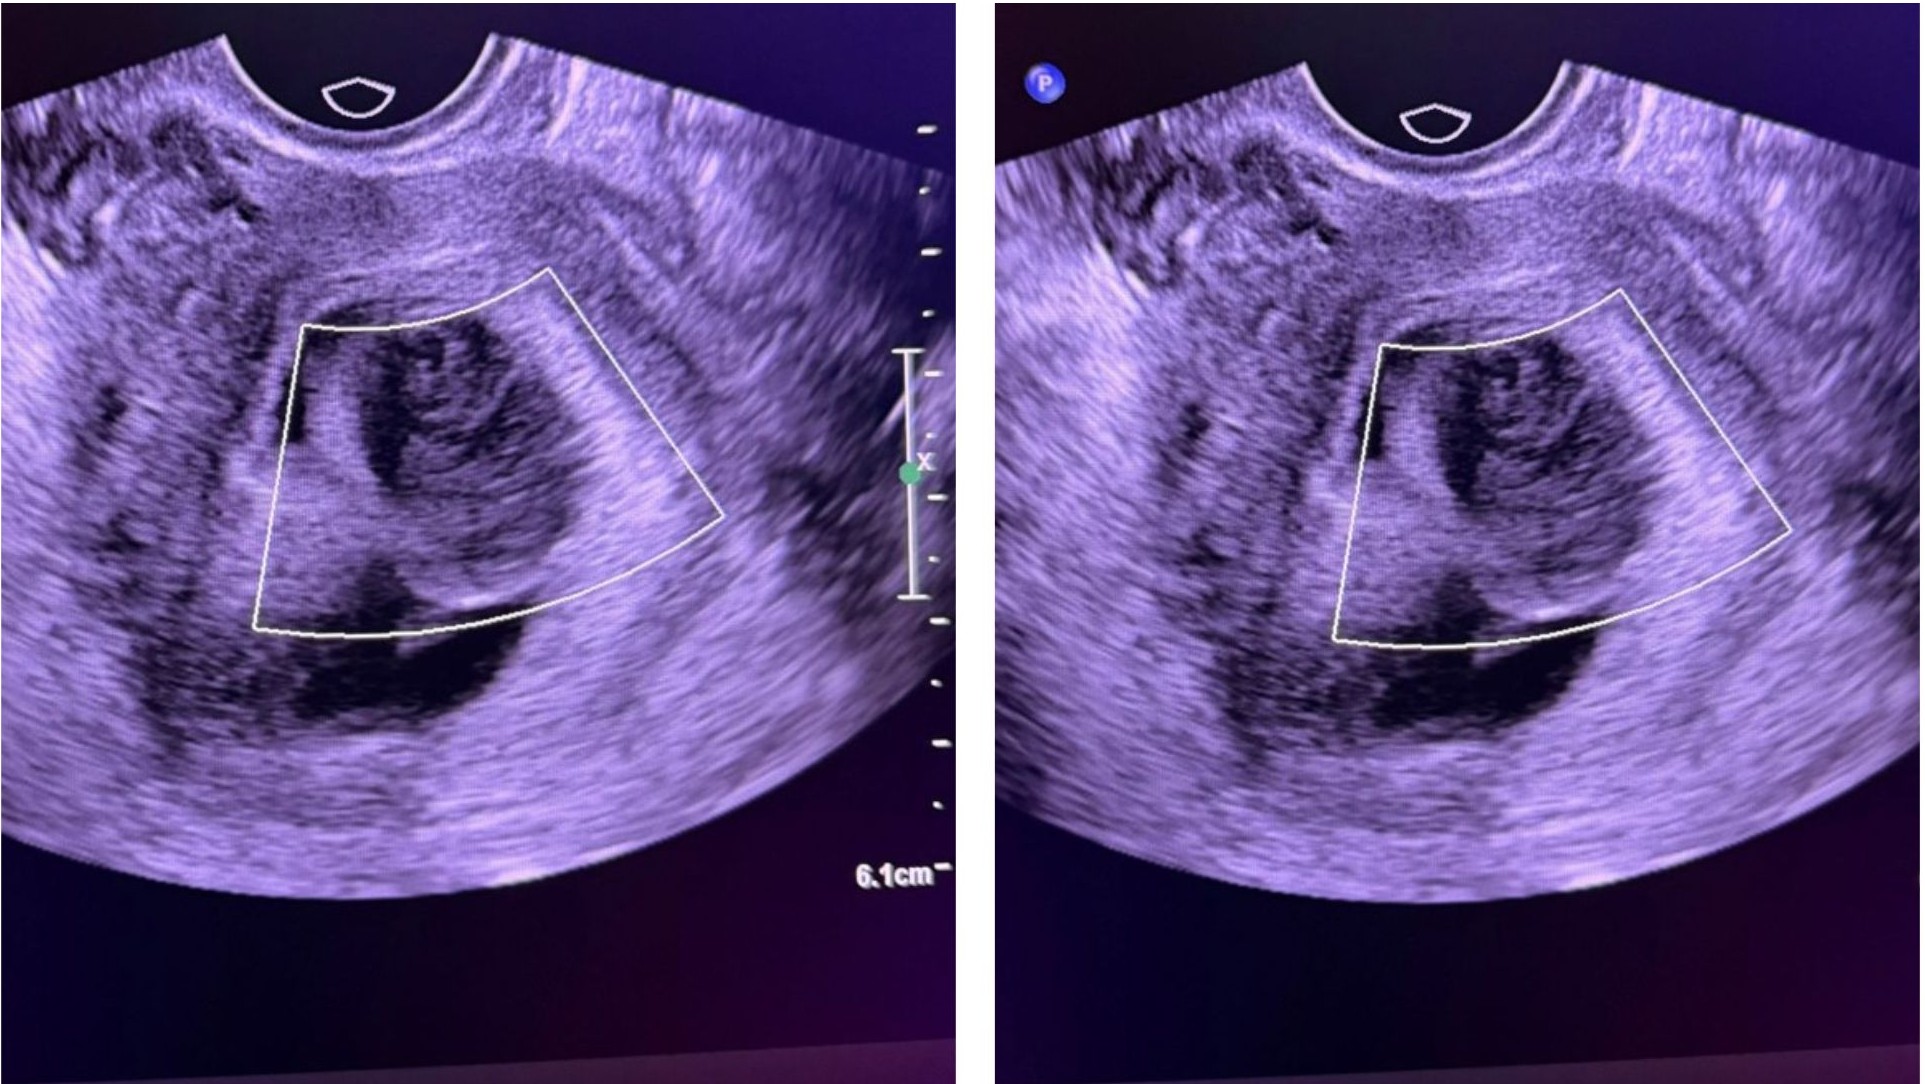

No internal vascularity on Color Doppler

Irregular, convex soft-tissue bulge projecting from the choriodecidual surface

Isoechoic or heteroechoic compared to chorion

Avascular on Color Doppler

No associated subchorionic hematoma